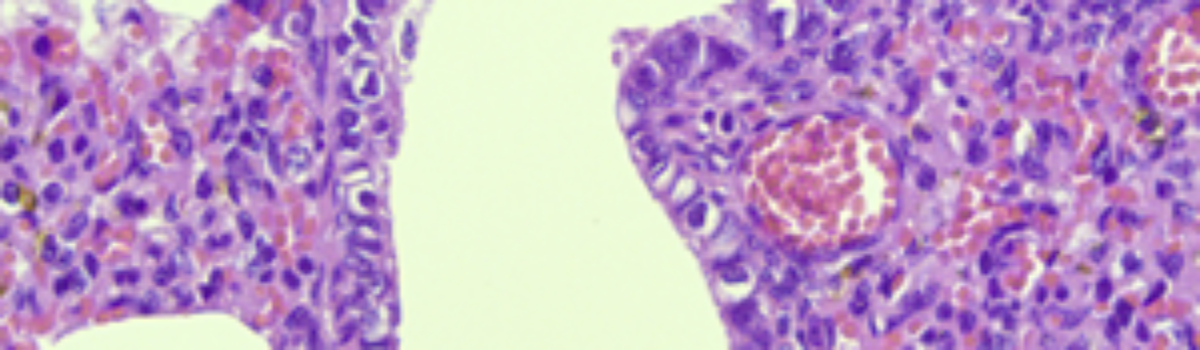

PRRS, wywoływany przez arteriwirusa, należy do najczęściej występujących chorób zakaźnych trzody chlewnej na świecie. Cechą charakterystyczną wirusa PRRSV jest jego zdolność do licznych mutacji i rekombinacji, co ostatecznie prowadzi do powstania nowych wariantów wirusa. Główną drogą transmisji PRRSV jest zakażona świnia i skażone nasienie. Badania kontrolowane wykazały, że zakażone świnie mogą być długoterminowymi nosicielami; dorosłe osobniki mogą wydalać PRRSV do 86 dni po zakażeniu, a odsadzone prosięta mogą być nosicielami wirusa przez 157 dni. Odnotowano transmisję PRRSV drogą aerozolową na odległość 9,1 km. Czynniki środowiskowe sprzyjające transmisji PRRSV obejmują korzystny kierunek wiatru, słabe nasłonecznienie i temperaturę powietrza zbliżoną do 0°C. PRRSV może być również przenoszony przez przedmioty, takie jak skażone igły, buty, kombinezony, pojazdy transportowe i kontenery transportowe. Wirus uszkadza makrofagi, co prowadzi do immunosupresji i predysponuje do wtórnych zakażeń układu oddechowego. W diagnostyce histopatologicznej podstawowym materiałem są płuca, a także migdałki oraz węzły chłonne krezkowe i pachwinowe. Charakterystyczną zmianą mikroskopową jest śródmiąższowe zapalenie płuc.

Rycina 1. Tkanka płucna w obrazie histopatologicznym